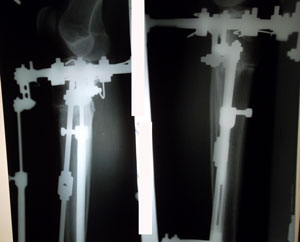

Re: Ножки с обложки!

Дата операции 18.11.2014г.

Дата снятия аппаратов 23.02.2015г.

Срок лечения 95 дней.